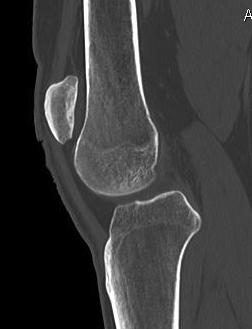

- clinical and xray patella tilt

1. Arthroscopic lateral release

- knee in extension

- camera in AM portal

- hook diathermy in AL portal

- 5mm lateral to patella / 1cm superior to patella / down to anterolateral portal

- release retinaculum under vision

- must ensure SLGA coagulated / can visualise

- let down tourniquet at end of procedure

- ensure can evert patella 90o at end